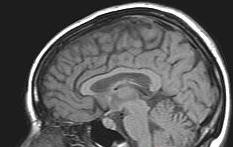

Stroke is the third leading cause of death in the United States and the leading cause of adult disability.